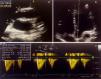

Se considera que un paciente «responde a los líquidos» cuando es capaz de aumentar su índice cardiaco de forma significativa (>10%) con una carga de líquido6. El TEPP es una maniobra que intenta reproducir transitoriamente los efectos de una carga de líquidos mediante la movilización de la sangre venosa de las piernas (unos 300ml en adultos) hacia la circulación central. Para realizarlo es necesario primero hacer una medición basal del VL mediante ecocardiografía con la cabecera de la cama a 45° respecto de las piernas. A continuación, se procede al descenso de la cabecera y la elevación de las piernas a 45° grados. Tras 60-120s en esta posición, se repite la medición del VL. Un aumento del VL >12% predice con una alta fiabilidad la respuesta positiva los líquidos7. Es conveniente verificar la respuesta con una nueva medición del VL tras la expansión. La respuesta y el cálculo del VL durante del TEPP se resumen en la tabla 1 y la figura 1.

Cálculo del volumen latido por ecocardiografía. Se precisa la medición del tracto de salida ventricular izquierdo (D) en un corte paraesternal eje largo (a), en un plano apical 5 cámaras se coloca el Doppler en la válvula aórtica (b) y se traza la integral velocidad-tiempo (VTI) obtenida (c). El ecógrafo calcula automáticamente el volumen latido mediante la siguiente fórmula: VL (ml) = π×(D/2)2×VTI. Conociendo la frecuencia cardiaca y la superficie corporal se deriva el índice cardiaco (IC=VL×FC).